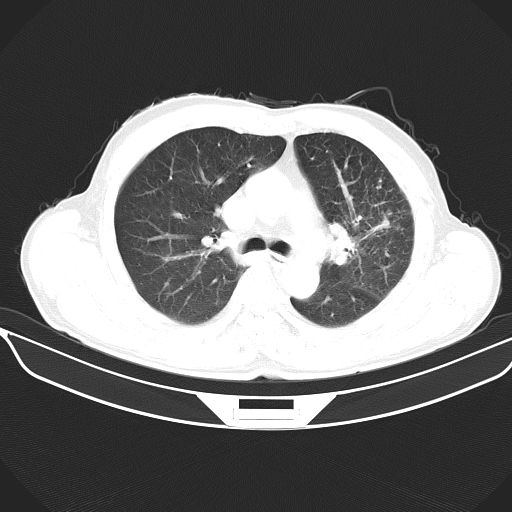

以下是引用心路寻觅在2010-3-1 10:23:00的发言:[br]1、考虑左肺上叶周围型肺癌[br]2、右上肺陈旧性病灶。[br][br][本贴已被 心路寻觅 于 2010-3-1 10:40:18 修改过]

以下是引用shuiyuan在2010-3-1 10:45:00的发言:[br]考虑左肺上叶中心型肺癌伴阻塞型炎症,邻近胸膜受侵。